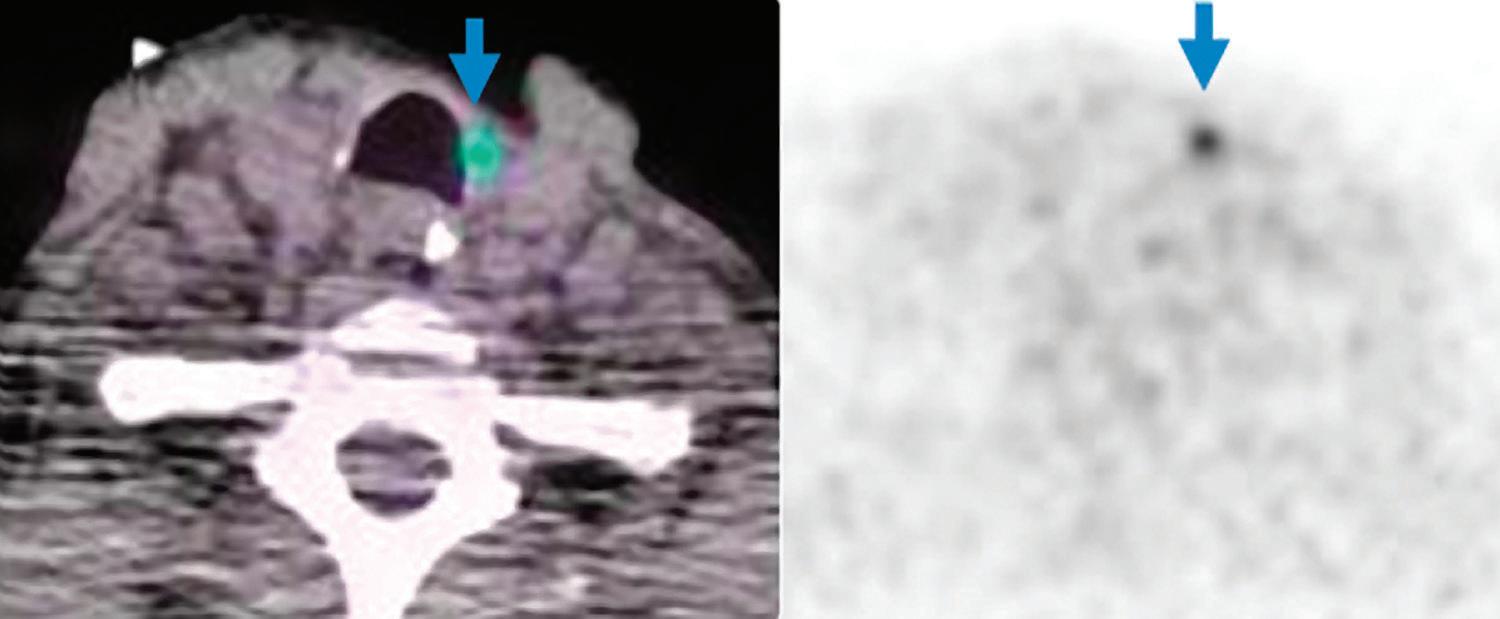

Iodine overlay axial image: better delineation of left paratracheal mass in thyroid bed with higher iodine content (arrow).

high metabolic activity within the left paratracheal mass in thyroid bed (SUVmax 4.8, blue arrows).

Iodine overlay coronal image: better delineation of left level IIa enlarged lymph node with higher iodine content (arrow).

PET/CT axial images:

PET/CT coronal images: high metabolic activity within the left level IIa enlarged lymph node (SUVmax 10.4, arrows).